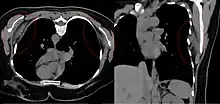

Bilateral elastofibroma dorsi in native computed tomography: left image axial in prone position (for biopsy), right image oblique coronal view.

By computed tomography, there is a poorly circumscribed, heterogeneous soft tissue mass, with a signal intensity similar to skeletal muscle. The fact that the lesion may be bilateral, helps eliminate a sarcoma from further consideration.[5] At US, elastofibromas are depicted deep to the musculature as a multilayered pattern of hypoechoic linear areas of fat deposition intermixed with echogenic fibroelastic tissue.[6] The mass often protrudes from the subscapular region upon shoulder abduction, allowing better delineation of the finding.[7]